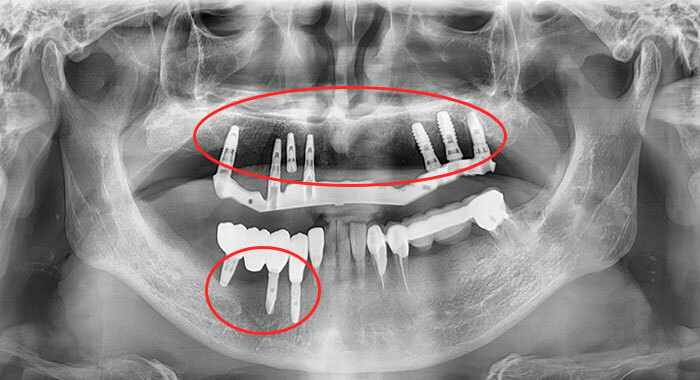

71歳

私の父のレントゲン

自分の歯7本

それ以外インプラント(赤枠部分〇)

43歳

私のレントゲン

自分の歯28本

治療痕9本(中学・高校で油断しました)

父と私のレントゲンどちらが生活に不自由ないと思いますか?

違いは父は歯科医であり祖父母は歯科医ではなかったということです。

要するに虫歯のできる原因は遺伝ではなく環境です。